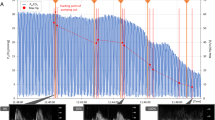

The Pei values at t30 (end of the baseline CV period) and later are shown in Fig. 1. Pei remained steady in the CV groups. It increased when 30 cmH2O Pei ventilation was initiated, but significantly less in the presence of terbutaline (p < 0.001 at 90 and 120 min). Pei remained steady in the presence of PEEP, and even decreased to be significantly lower at 120 min (p < 0.001) when terbutaline was given IT. After an initial increase, Pei remained steady during HV at 25 cmH2O Pei whether terbutaline was given IP or not.

Changes in end-inspiratory pressure (Pei) during ventilation with terbutaline (T) given in the instillate (intra-tracheally, IT) or intra-peritoneally (IP) or without terbutaline. Pei was similar in all groups during the 30-min conventional ventilation (CV) period and stayed low in animals ventilated with this modality. Pei increased sharply in rats ventilated with a high volume at 30 cmH2O Pei (HV1), either in the absence or the presence of PEEP (HV2P), but not at 25 cmH2O Pei and no PEEP (HV2). Intra-tracheal terbutaline significantly decreased Pei in animals ventilated at 30 cmH2O Pei (p < 0.001 at 90 and 120 min)

Alveolar 99mTc-albumin permeability

CV was not accompanied by significant 99mTc-albumin leakage from airspaces. Terbutaline IT had no effect on albumin permeability during CV. HV produced an immediate decrease in lung 99mTc-albumin content, as previously reported [15], which was lessened by PEEP (Fig. 4, p < 0.01). Terbutaline IT significantly reduced the increase in albumin permeability due to HV ventilation, regardless of the presence of PEEP, as shown in Fig. 5. Albumin permeability in the presence of PEEP + terbutaline IT was higher, but not significantly so, than that in CV controls. Terbutaline IP did not affect the increase in alveolar albumin permeability due to 25 cmH2O Pei ventilation.

Changes in lung 99mTc-albumin content (pooled values) during conventional ventilation (open circles), high-volume ventilation at 30 cmH2O without PEEP (open squares) and the same ventilation modality in animals given terbutaline in the instillate (filled squares). Terbutaline lessened the leakage of albumin from alveolar spaces produced by high-volume ventilation. The same observation was made during high-volume ventilation with PEEP. Terbutaline given intra-peritoneally did not change alveolar albumin leakage

Alveolar 99mTc-albumin permeability surface area product (PSA, log scale) calculated from the initial slopes of the curves shown in Fig. 4. PSA was nearly 1,000 times higher (p < 0.001) during high-volume ventilation at 30 (HV1) or 25 cmH2O (HV2) end-inspiratory pressure than during conventional (CV) ventilation, irrespective of the presence of PEEP (HV1P). Terbutaline given in the instillate (intra-tracheally, IT), but not intra-peritoneally (IP), reduced PSA when increased by high-volume ventilation (*p < 0.05 compared with the same ventilation modality)